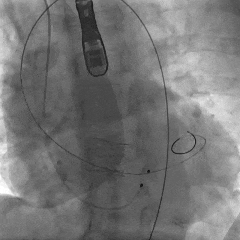

根部造影,瓣叶活动差

20mm球囊预扩,微腰微漏

输送器过弓

snare辅助下跨瓣

瓣膜初始定位

第一次释放,瓣膜位置偏高,选择回收

第二次瓣膜释放

造影评估,瓣膜位置可

右侧位造影,瓣膜深度可

多角度评估,瓣膜位置可,少量瓣周漏